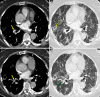

Results: The study population comprised 82 men and 19 women, with a mean age of 64.1 years ± 15.0 (95% confidence interval [CI]: 60.4, 67.6) years. CT pulmonary angiography was performed 19.8 days ± 6.1 (95% CI: 18.1, 20.2) after symptom onset and 10.5 days ± 3.8 (95% CI: 10.2, 12.9) after admission. Of 101 patients, 41 had PTE (40.6%). PTE was mostly bilateral or only right (37/41 [90.2%]), mainly involved segmental (37/41 [90.2%]) or subsegmental (25/41 [61.0%]) arteries and affected mainly the branches of the lower lobe (30/41 [73.2%]). Parenchymal segments supplied by segmental arteries with PTE showed a prevalent consolidation pattern (25/37 [67.6%]). Deep vein thrombosis was present only in five of 41 (12.2%) patients. Comparing groups with and without PTE, no significant difference was observed in age, sex, symptom onset, comorbidities, tumor history, use of respiratory supports, activated partial thromboplastin time, prothrombin time, and deep vein thrombosis. Conversely, differences were evaluated in CT lesion score (15.7 ± 1.4 [95% CI: 15.3, 16.1] vs 14.1 ± 1.1 [95% CI: 13.8, 14.4]; P = .035), d-dimer level (P < .001), lactate dehydrogenase level (P < .001), and C-reactive protein level (P = .042).

Conclusion: PTE in COVID-19 involves mainly the segmental and subsegmental arteries of segments affected by consolidations in patients with more severe lung disease. The authors hypothesize that the development of PTE in COVID-19 might be a pulmonary artery thrombosis because of severe lung inflammation and hypercoagulability rather than thromboembolism.© RSNA, 2020.